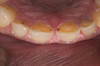

Figure 1 Normal overjet/overbite of anterior teeth

Figure 1